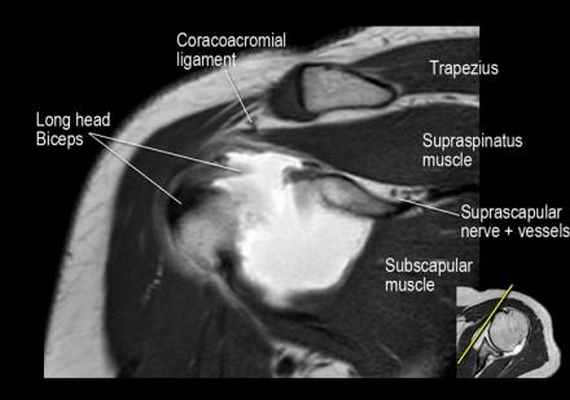

Нормальная корональная анатомия плечевого сустава и контрольный список

- обратите внимание на надлопаточный нерв и сосуды (suprascapular nerve and vessels)

- поищите импинджмент надостной мышцы за счет остеофитов в акромиально ключичном суставе или из-за утолщения клювовидноакромиальной связки.

- изучите верхний комплекс двуглавой мышцы и суставной губы, поищите подгубный карман илм SLAP-повреждение

- поищите скопление жидкости в подакромиальной сумке и повреждение сухожидия надостной мышцы